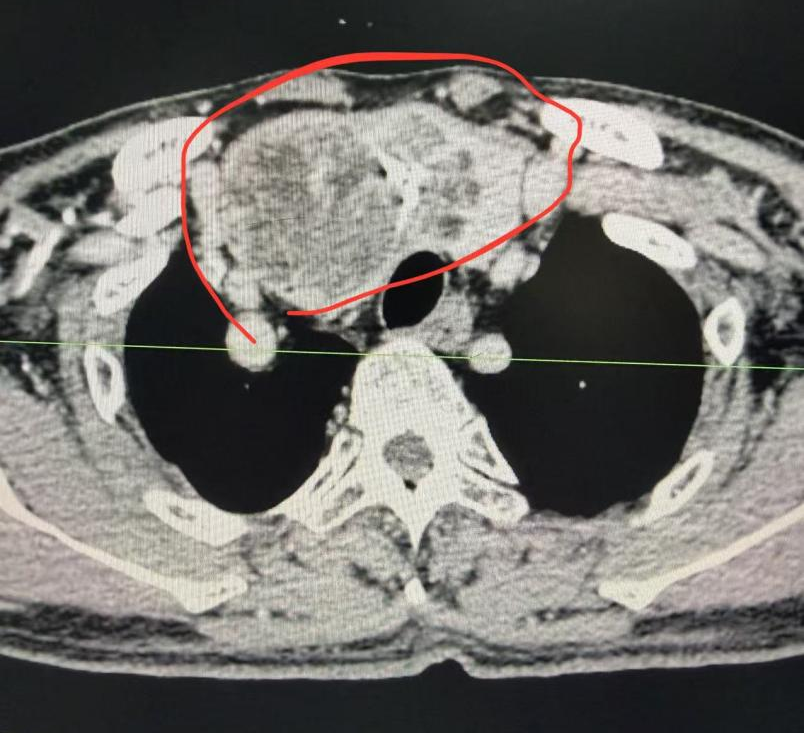

红网时刻新闻4月13日讯(通讯员 王环)近日,62岁患者邹某某因严重呼吸困难,慕名来到衡阳市中心医院乳甲外科,找到科室主任罗琼博士求诊。经CT检查发现,邹某某患有胸骨后巨大甲状腺肿,气管被严重挤压偏移,最窄处仅剩正常管径的三分之一,手术风险极高。

面对高龄、基础疾病多、麻醉插管困难等多重挑战,罗琼博士团队联合麻醉科、重症医学科等多学科专家制定周密方案。术中,罗琼博士凭借精湛解剖技术,在未开胸的情况下完整切除大小约8cm×6cm的肿物,出血不足30毫升,并成功保护了喉返神经及甲状旁腺功能。患者术后恢复良好,已顺利出院。